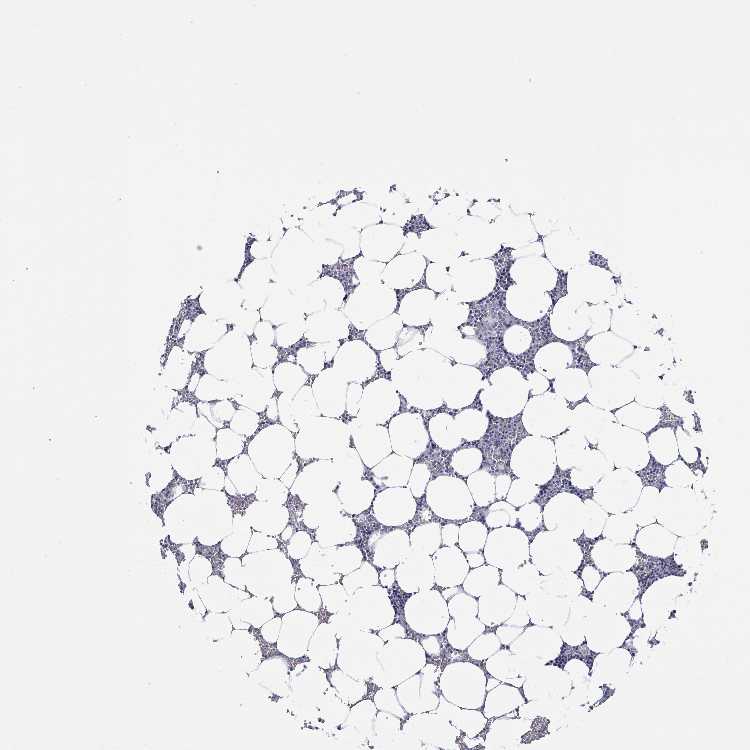

BONE MARROW - Antibody stainingi

Antibody staining in the annotated cell types in the current human tissue is reported as not detected, low, medium, or high, based on conventional immunohistochemistry profiling in selected tissues. This score is based on the combination of the staining intensity and fraction of stained cells.

Each image is clickable and will lead to virtual microscopy that enables deeper exploration of all samples and also displays staining intensity scores, fraction scores and subcellular localization as well as patient and tissue information for each sample.

Antibody HPA046672

Hematopoietic cells Not detected